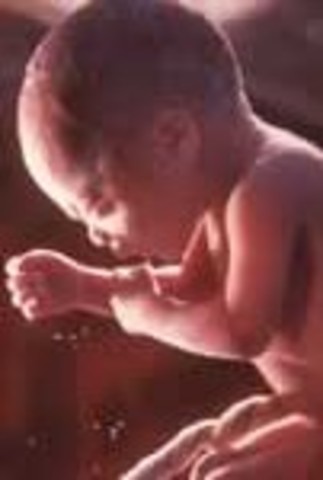

• week32

week32

• Under the skin the fat layer is getting thicker.

• The toenails and fingernails are completely formed.

• In boys, the testicles will be descending from the groin down into his scrotum

• week 33

week 33

• The baby fuzz is disappearing.

• Your baby drinks about a pint of amniotic fluid a day.

• week35

week35

• The body of your baby is growing round due to developing fat layers.

• Your baby's reflexes are coordinated.

• Lungs are almost fully developed.

• About 90% of babies born this week survive